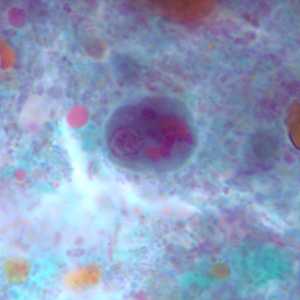

I. buetschlii cysts stained with trichrome.

Figure A: Cyst of I. buetschlii stained with trichrome. In this specimen, both the nucleus and large glycogen vacuole are visible.

Figure B: Cyst of I. buetschlii stained with trichrome. In this specimen, both the nucleus and large glycogen vacuole are visible.

Figure C: Cyst of I. buetschlii stained with trichrome. In this specimen, both the nucleus and large glycogen vacuole are visible (arrow).

Figure D: Cyst of I. buetschlii stained with trichrome. In this specimen, both the nucleus and large glycogen vacuole are visible.